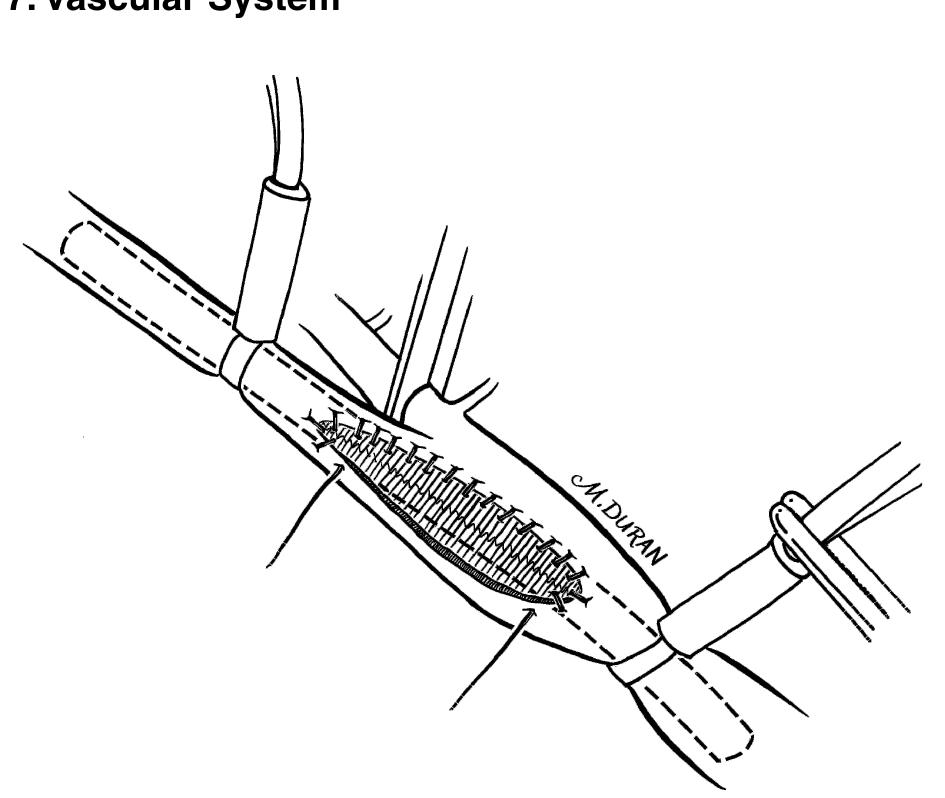

The paper discusses the surgical anatomy and techniques associated with various procedures, with particular emphasis on the anatomy of the scalp, including its vascular, lymphatic, and nerve supplies. It presents detailed insights into the blood supply of the scalp, highlighting the important arterial branches and their anastomoses, as well as the implications for surgical procedures. Additionally, the paper outlines techniques for surgical interventions, positioning, and considerations necessary for effective outcomes.